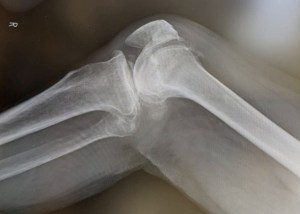

私の場合で言うと、前十字靭帯が切れて、時間とともに縮んでしまって二度と自力では再生しない状態=関節を繋ぐものが一本消失した状態で症状固定してしまったということです。

とはいえ、関節を固定するものがないですから、半月板が傷みまくりにもなります。

通常半月板に傷がつきますと、高潤滑のベアリングに傷が入るのと同じで、動きに対して引っかかりが生じます。

半月板の場合、膝を曲げたら曲げたまま、伸ばしたら伸ばしたままにロックがかかることがあります。

しかし、私の膝は半月板に傷がついて動きが悪くなるはずなのですが、靱帯がないので引っかかりがなく、痛いのだけど膝は動きます。

後遺症診断には膝の曲がる角度の検査や触診の廻旋テストや前方引き出しテストというものが行われます。

要は、足を伸ばしたり曲げたり回したりして緩みを判断するのですがどの診断もつい力が入って思うように診断ができません。

足関節の不安定性を診るテストです。

前方引き出しテストとは、レントゲン室で負荷のない時とひざを曲げて足を突いた状態でおもいっきり引っ張った状態を撮影して誤差を測る検査です。